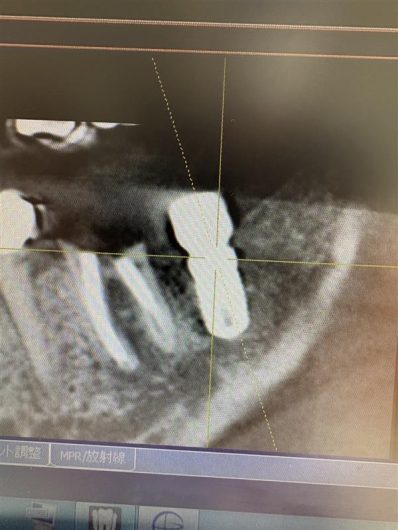

一番奥の歯を抜いたま長年放置してしまった為手前の歯に負担がかかってしまい割れて神経が死んでしまいました。神経の治療を完了した後に無くなっていた一番奥の歯があった場所にインプラントを埋める計画となりました。

プランニング通り正しい位置に埋める事が出来ました。